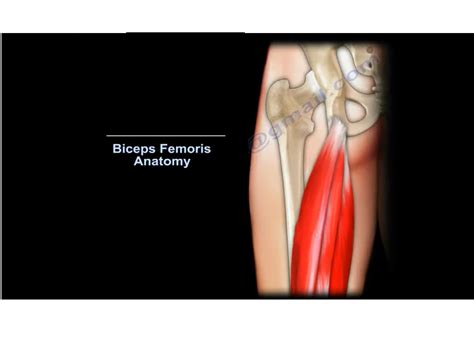

Understanding Biceps Femoris Tendinosis

Biceps Femoris Tendinosis is a degenerative condition that affects the tendon of the biceps femoris muscle, one of the three muscles that make up the hamstring. This condition is characterized by the degeneration of the tendon tissue, leading to pain and weakness in the back of the thigh. It is often caused by repetitive stress and overuse, making it common among athletes involved in sports that require sudden stops, starts, and changes in direction, such as soccer, basketball, and track and field.